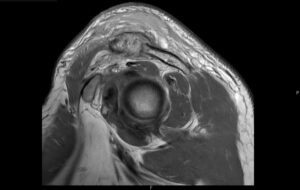

Septic Arthritis of AC Joint. MRI Sagittal. Unannotated. JETem 2024